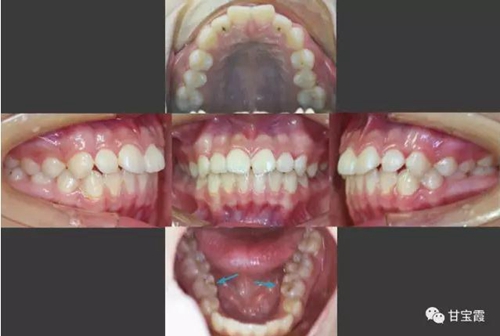

下面的矯正前后的對比照片看出側(cè)貌得到了改善

6.jpg

矯正前后的面相顯示小女孩變得更漂亮了。